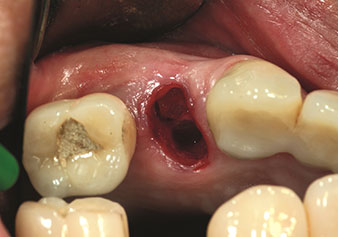

Alveolar management

One application, which is often underestimated is the atraumatic extraction of tooth roots or root fragments in the scope of alveolar management. The fine periotomes, which are currently available in two versions (EX1 and EX2 from W&H), can also be used to remove teeth which have previously undergone special endodontic treatment or ankylosed roots with ease. This results in extraction alveoli where both the hard and soft tissue are fully intact as it is generally possible to avoid reflection.

This establishes the optimal basis for subsequent or immediate implant treatment (Figures 1 and 2 included with the kind permission of Dr Torsten Conrad, Bingen a. Rhein).

Fine periotome (EX1 instrument)

Fig. 1: Fine periotome (EX1 instrument).

Photo: © Dr Torsten Conrad (Bingen a. Rhein)